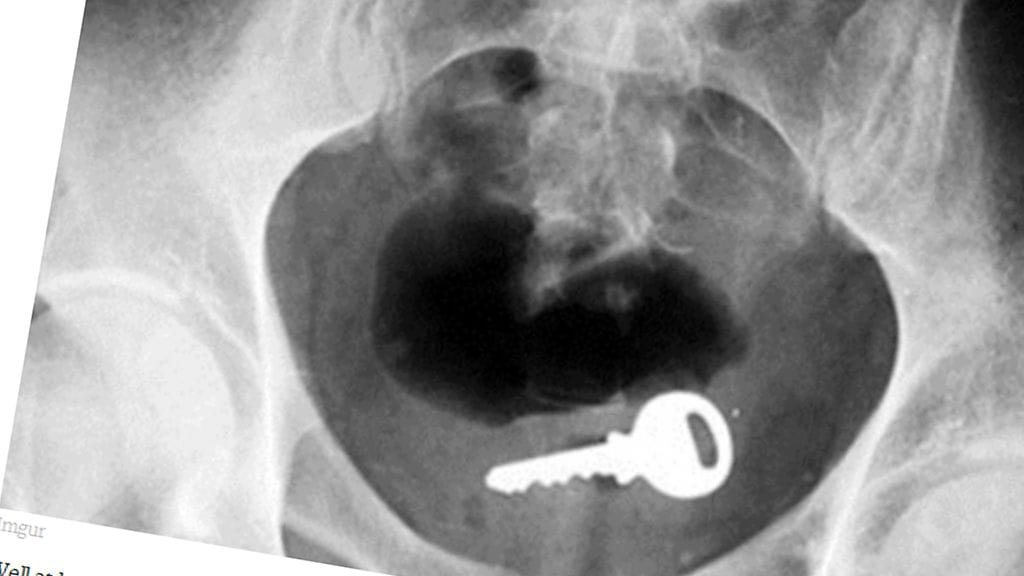

Erikoiset röntgenkuvat saavat ihmettelemään vain yhtä asiaa: voivatko ihmiset oikeasti olla näin typeriä?

Mikä menee sisään, ei välttämättä tule ulos ihan itsestään. Unilad-sivuston julkaisemat röntgen-kuvat asioista, joita himokkaat miehet ovat sisäänsä tunkeneet, eivät ensituntumalta vaikuta edes mahdollisilta.